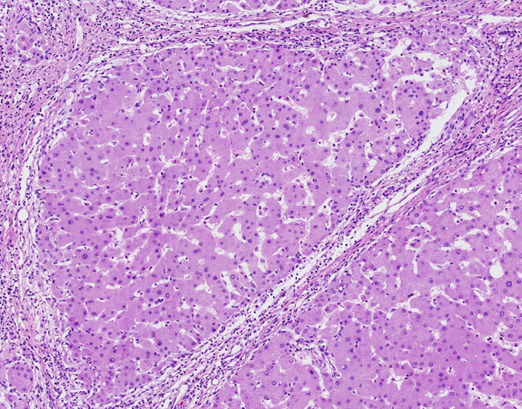

(二)镜下:1.假小叶形成。正常肝小叶结构被破坏,由广泛增生的纤维组织将原来的肝小叶分割包绕成大小不等、圆形或椭圆形的肝细胞团。2.纤维间隔宽窄较一致,内有少量淋巴细胞、单核细胞浸润,并可见小胆管增生。

假小叶:

定义:肝硬化时,正常肝小叶结构被破坏,由广泛增生的纤维组织将肝细胞再生结节分割包绕成大小不等、圆形或椭圆形的肝细胞团。

特点:*大小不一,排列紊乱

*中央静脉缺如或偏位

*肝细胞变性或坏死、再生